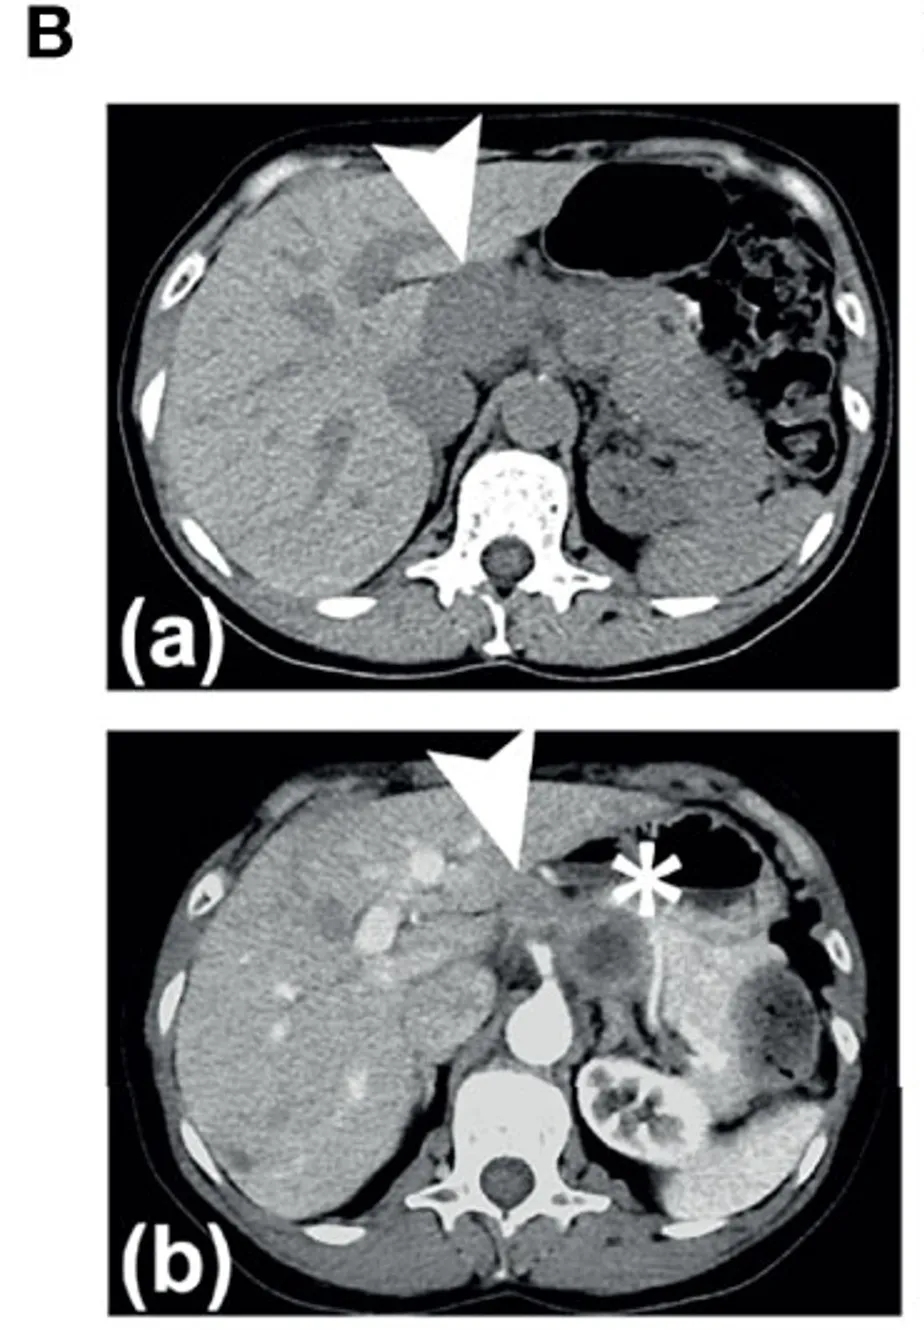

还有一例HER2阳性胃癌患者(患者9,HER2IHC3+,FISH2.5):基线时(治疗前)靶病灶大小为4.7×1.9cm;在治疗16周时靶病灶体积缩小约50%(缩小至2.8×1.9cm);第24周进一步缩小至1.9×1.9cm(见图2B)。虽因非靶病灶进展未达PR标准,但显著体现了疫苗对HER2阳性胃癌的局部控制能力。